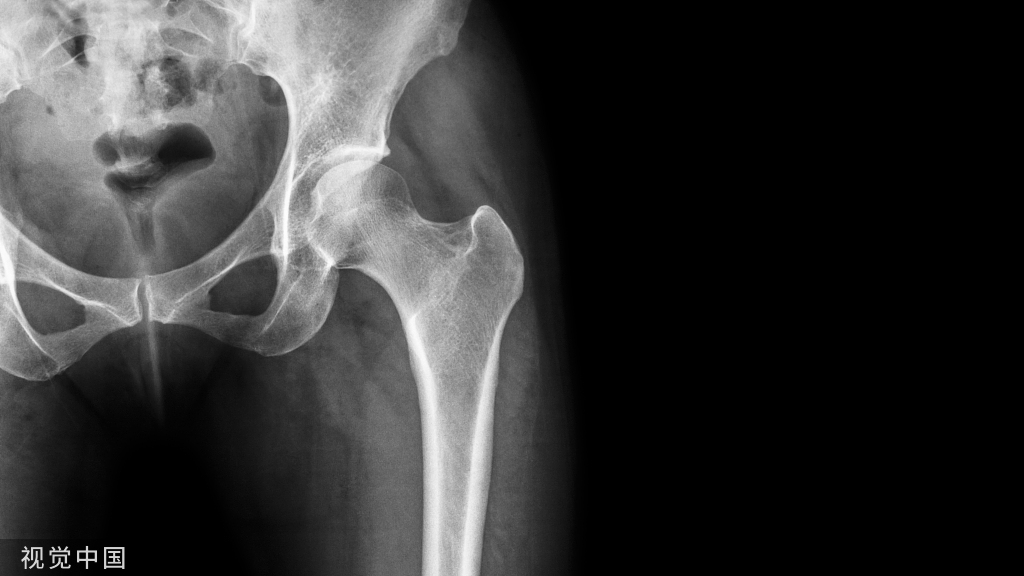

股骨远端骨折示例。沿股骨远端骨块作一中轴线,骨折线与中轴线相交,形成2锐角(Acute angles)。

2.经骨折线作一线与上述轴线相交;3.相交后形成夹角,辨认出锐角处;

胫骨近端骨折同理

4.将Poller置于锐角处的干骺端或远端骨块;

将Poller钉置于锐角处。

胫骨近端骨折,同理将Poller钉置于锐角处。5.置入导致,透视下确保通过Poller钉纠正移位;6.置入主钉。